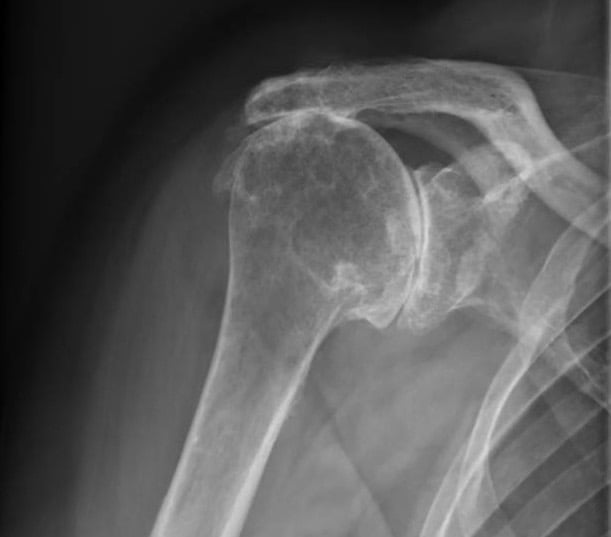

Vous présentez une arthrose de l'épaule / gléno-humérale ; avec une coiffe des rotateurs parfaitement compétente.

Vous présentez une arthrose de l'épaule / gléno-humérale ; ET une coiffe des rotateurs détériorée (1)

La conséquence est une omarthrose / usure excentrée de l'épaule ( 2).